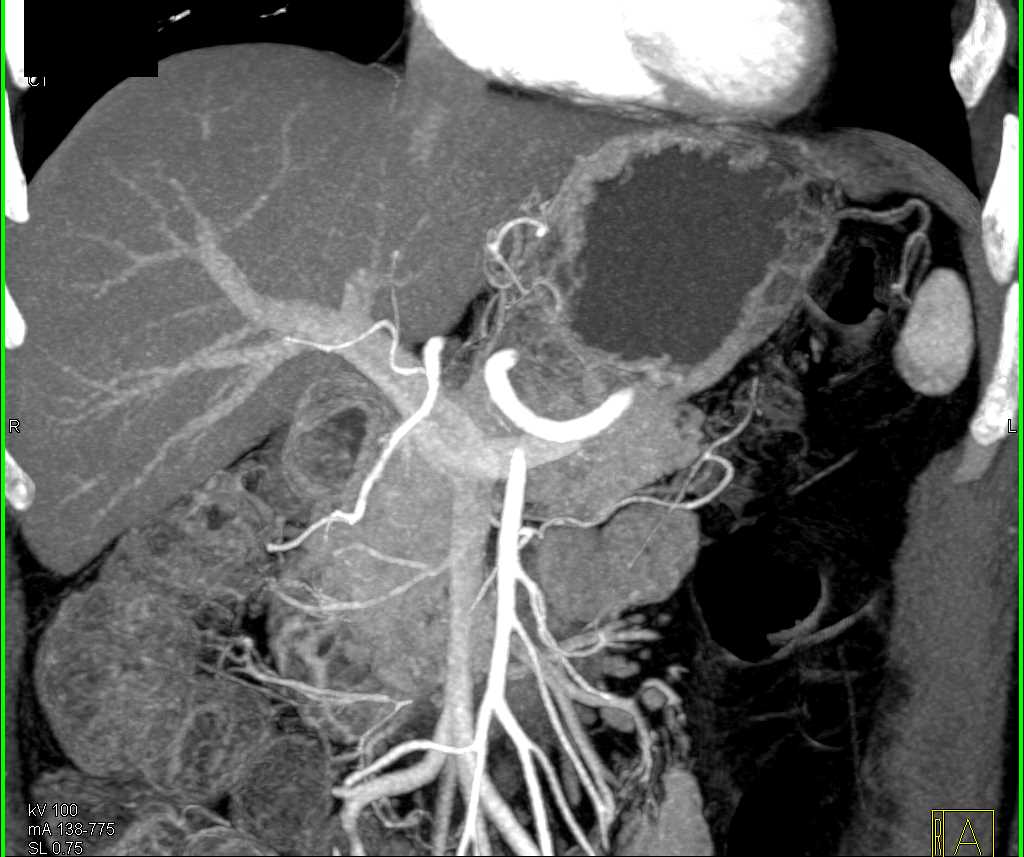

Duodenal Carcinoma with Obstruction